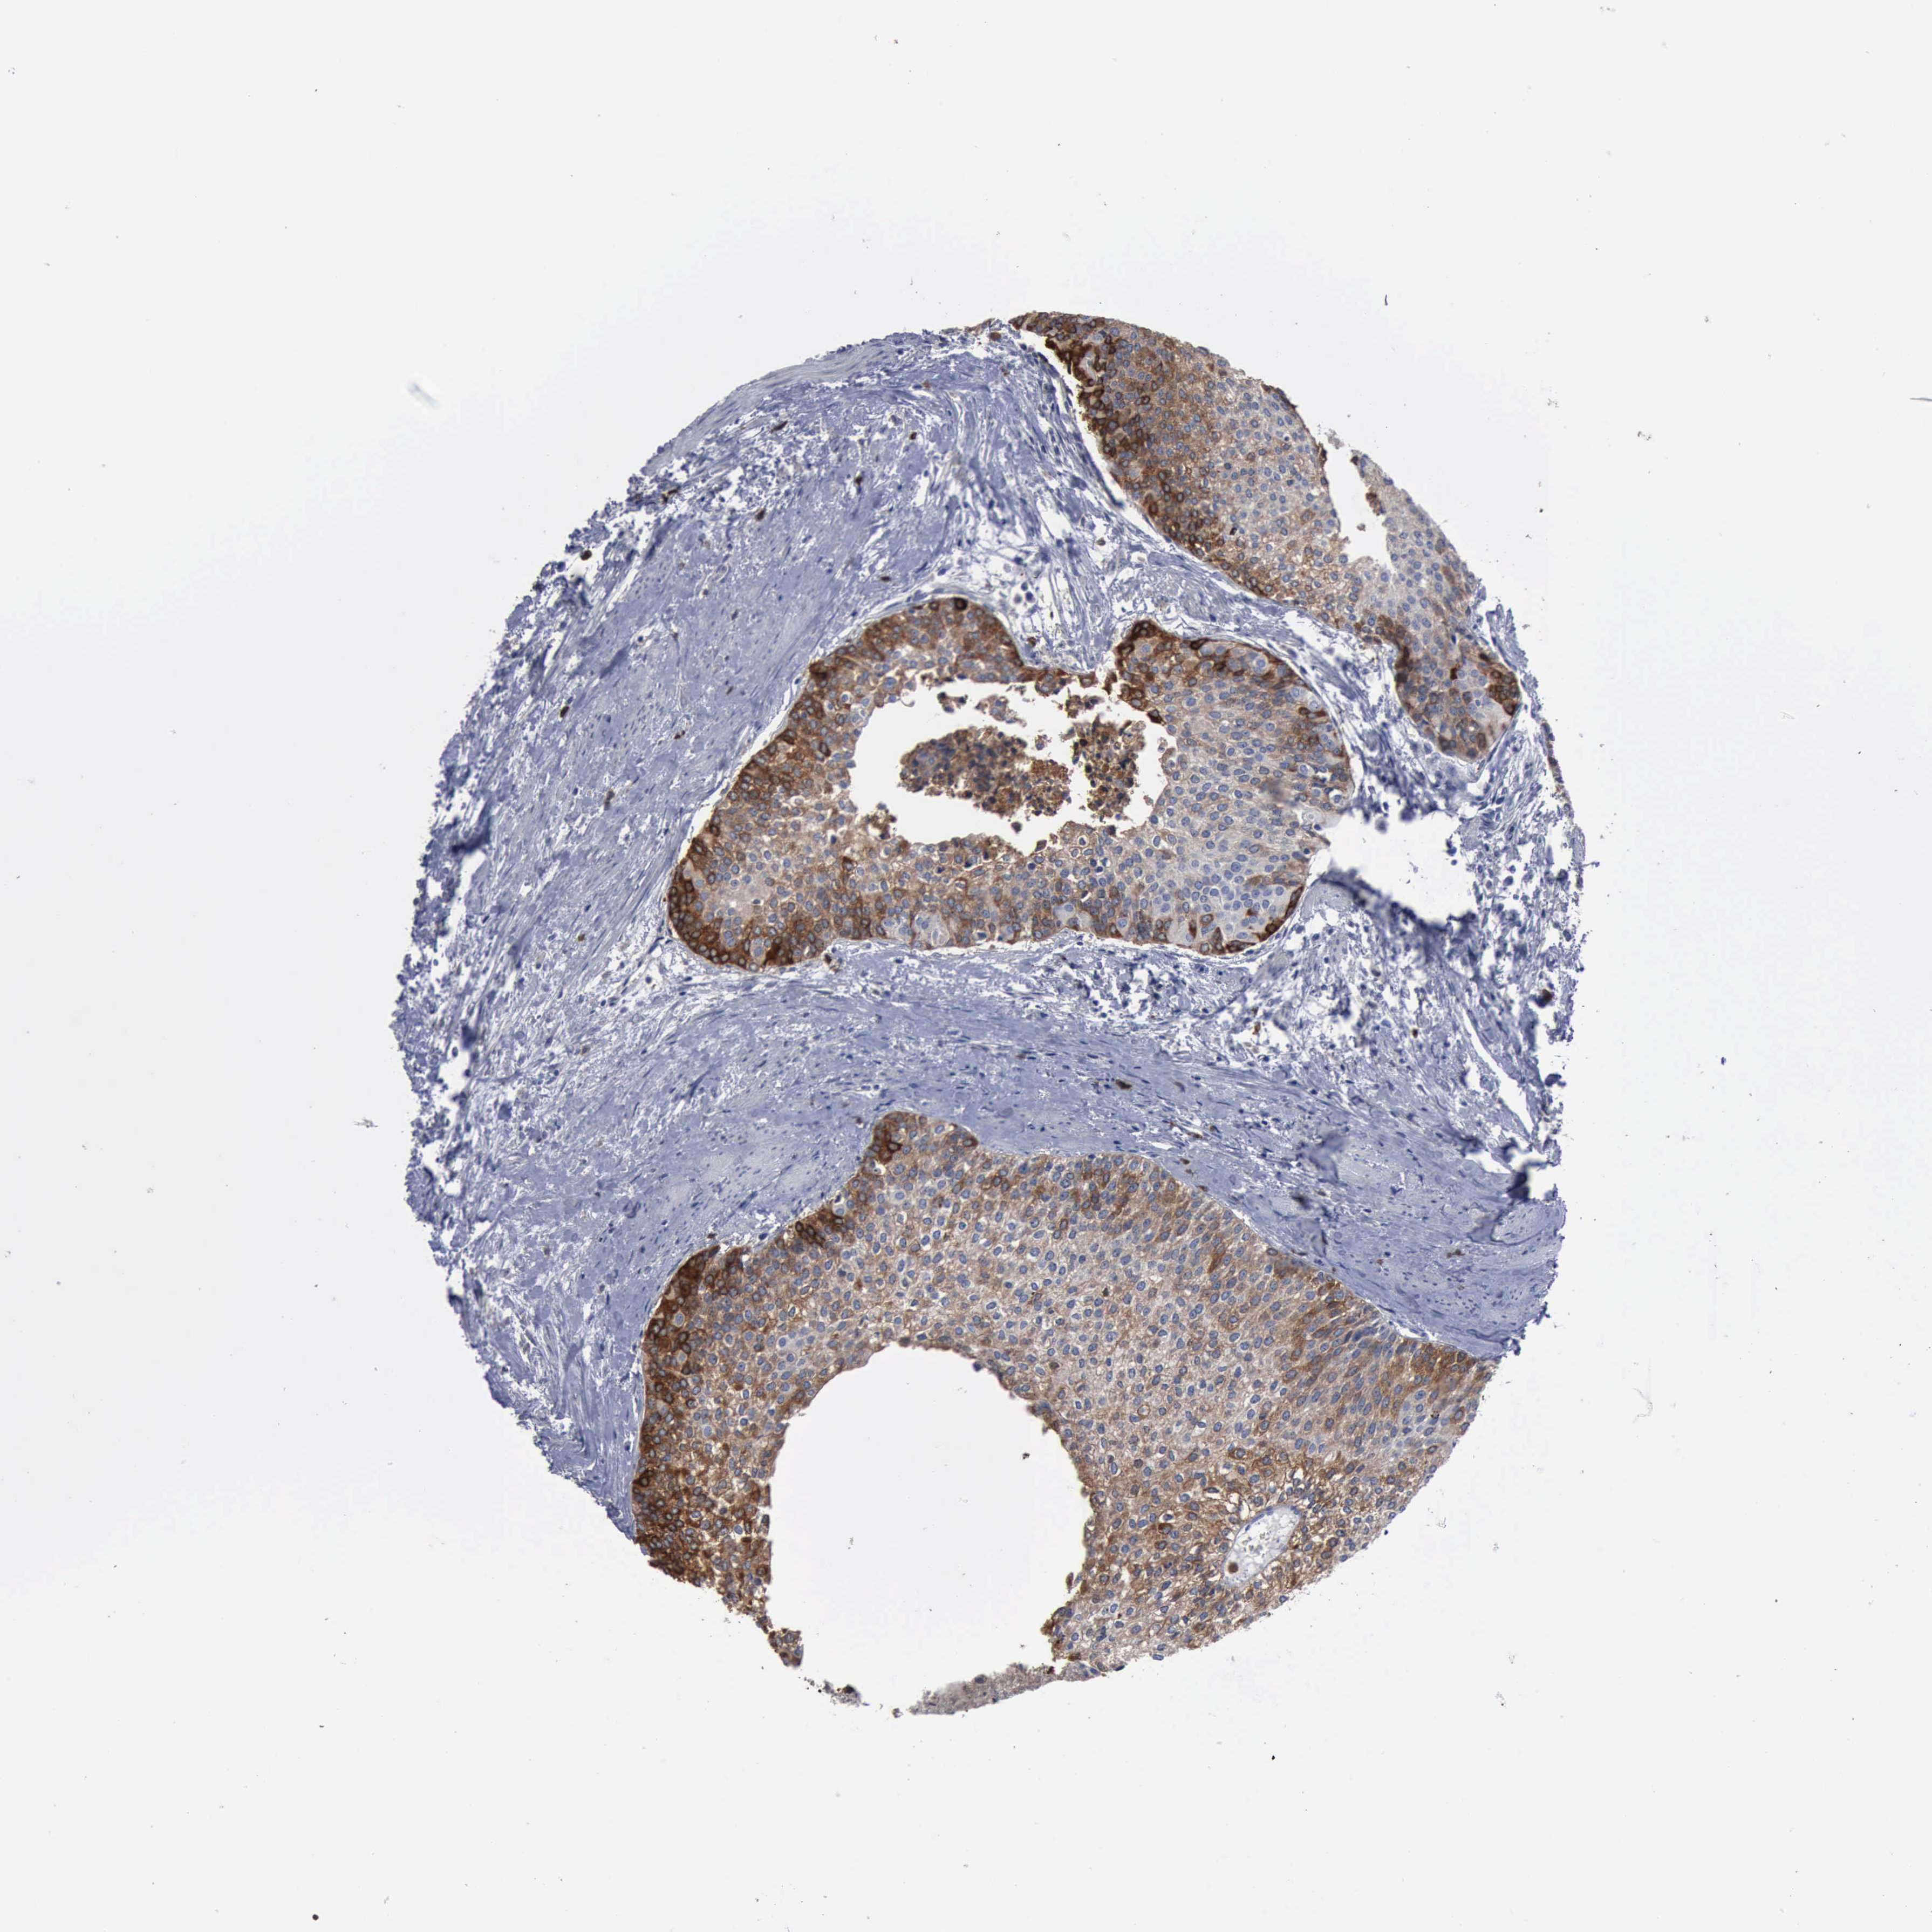

UROTHELIAL CANCER - Protein expressioni

A mouse-over function shows sample information and annotation data. Click on an image to view it in a full screen mode. Samples can be filtered based on level of antibody staining by selecting one or several of the following categories: high, medium, low and not detected. The assay and annotation is described here.

Note that samples used for immunohistochemistry by the Human Protein Atlas do not correspond to samples in the TCGA dataset.

Antibody stainingi

Antibody staining in the annotated cell types in the current human tissue is reported as not detected, low, medium, or high, based on conventional immunohistochemistry profiling in selected tissues. This score is based on the combination of the staining intensity and fraction of stained cells.

Each image is clickable and will lead to virtual microscopy that enables deeper exploration of all samples and also displays staining intensity scores, fraction scores and subcellular localization as well as patient and tissue information for each sample.

Antibody HPA000962

Antibody HPA004119

Staining

High

Medium

Low

Not detected

Intensity

Strong

Moderate

Weak

Negative

Quantity

>75%

75%-25%

<25%

None

Location

Nuclear

Cytoplasmic/membranous

Cytoplasmic/membranous,nuclear

Urothelial carcinoma, High grade

Urothelial carcinoma, Low grade

Adenocarcinoma, NOS